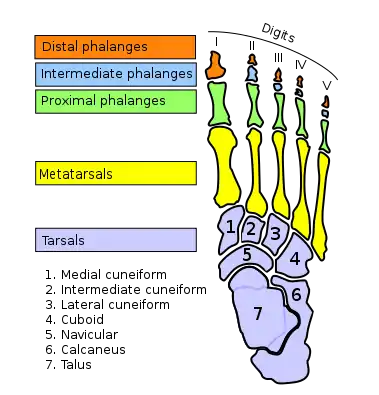

Skeleton of foot. Superior view. Metatarsals shown in green | |

The metatarsal bones, or metatarsus (pl.: metatarsi), are a group of five long bones in the midfoot, located between the tarsal bones (which forms the heel and the ankle) and the phalanges (toes). Lacking individual names, the metatarsal bones are numbered from the medial side (the side of the great toe): the first, second, third, fourth, and fifth metatarsal (often depicted with Roman numerals). The metatarsals are analogous to the metacarpal bones of the hand. The lengths of the metatarsal bones in humans are, in descending order, second, third, fourth, fifth, and first.[1] A bovine hind leg has two metatarsals.[2]

Structure

The five metatarsals are dorsal convex long bones consisting of a shaft or body, a base (proximally), and a head (distally).[3] The body is prismoid in form, tapers gradually from the tarsal to the phalangeal extremity, and is curved longitudinally, so as to be concave below, slightly convex above. The base or posterior extremity is wedge-shaped, articulating proximally with the tarsal bones, and by its sides with the contiguous metatarsal bones: its dorsal and plantar surfaces are rough for the attachment of ligaments. The head or distal extremity presents a convex articular surface, oblong from above downward, and extending farther backward below than above. Its sides are flattened, and on each is a depression, surmounted by a tubercle, for ligamentous attachment. Its plantar surface is grooved antero-posteriorly for the passage of the flexor tendons, and marked on either side by an articular eminence continuous with the terminal articular surface.[4]

Articulations

The base of each metatarsal bone articulates with one or more of the tarsal bones at the tarsometatarsal joints, and the head with one of the first row of phalanges at the metatarsophalangeal joints. Their bases also articulate with each other at the intermetatarsal joints

- The first metatarsal articulates with the medial cuneiform, and to a small extent to the intermediate cuneiform.[6]

- the second with all three cuneiforms.[6]

- the third with the lateral cuneiform.[6]

- the fourth with the lateral cuneiform and the cuboid.[6]

- The fifth with the cuboid.[6]